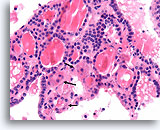

Afbeelding 13

Benigne, hyperplastisch/adenomatoïde nodule, schildklier FNA, celblok.

Het celblok dat overeenkomt met afbeelding 11-12 toont een duidelijk bijvoeging van micro- en macrofollikels. Er zijn twee kenmerken die voor een benigne nodule pleiten. Het eerste is dat de microfollikels afgeplat cytoplasma vertonen, vergeleken met de robuuster uitziende macrofolliculaire cellen (vergelijk de hoogte van het cytoplasma bij de twee pijlen). Een tweede kenmerk is de variatie in het uiterlijk van het colloïd tussen de verschillende follikels. Let op het oedemateuze colloïd in het ene follikel dat zich naast een follikel bevindt met dicht opeengepakt colloïd (open pijlen). Van benigne hyperplastisch/adenomatoïde nodulen wordt verwacht dat ze heterogeniteit vertonen, terwijl folliculaire neoplasmen monotoner zijn.

40X

Afbeelding 13

Benigne, hyperplastisch/adenomatoïde nodule, schildklier FNA, celblok.

Het celblok dat overeenkomt met afbeelding 11-12 toont een duidelijk bijvoeging van micro- en macrofollikels. Er zijn twee kenmerken die voor een benigne nodule pleiten. Het eerste is dat de microfollikels afgeplat cytoplasma vertonen, vergeleken met de robuuster uitziende macrofolliculaire cellen (vergelijk de hoogte van het cytoplasma bij de twee pijlen). Een tweede kenmerk is de variatie in het uiterlijk van het colloïd tussen de verschillende follikels. Let op het oedemateuze colloïd in het ene follikel dat zich naast een follikel bevindt met dicht opeengepakt colloïd (open pijlen). Van benigne hyperplastisch/adenomatoïde nodulen wordt verwacht dat ze heterogeniteit vertonen, terwijl folliculaire neoplasmen monotoner zijn.

40X